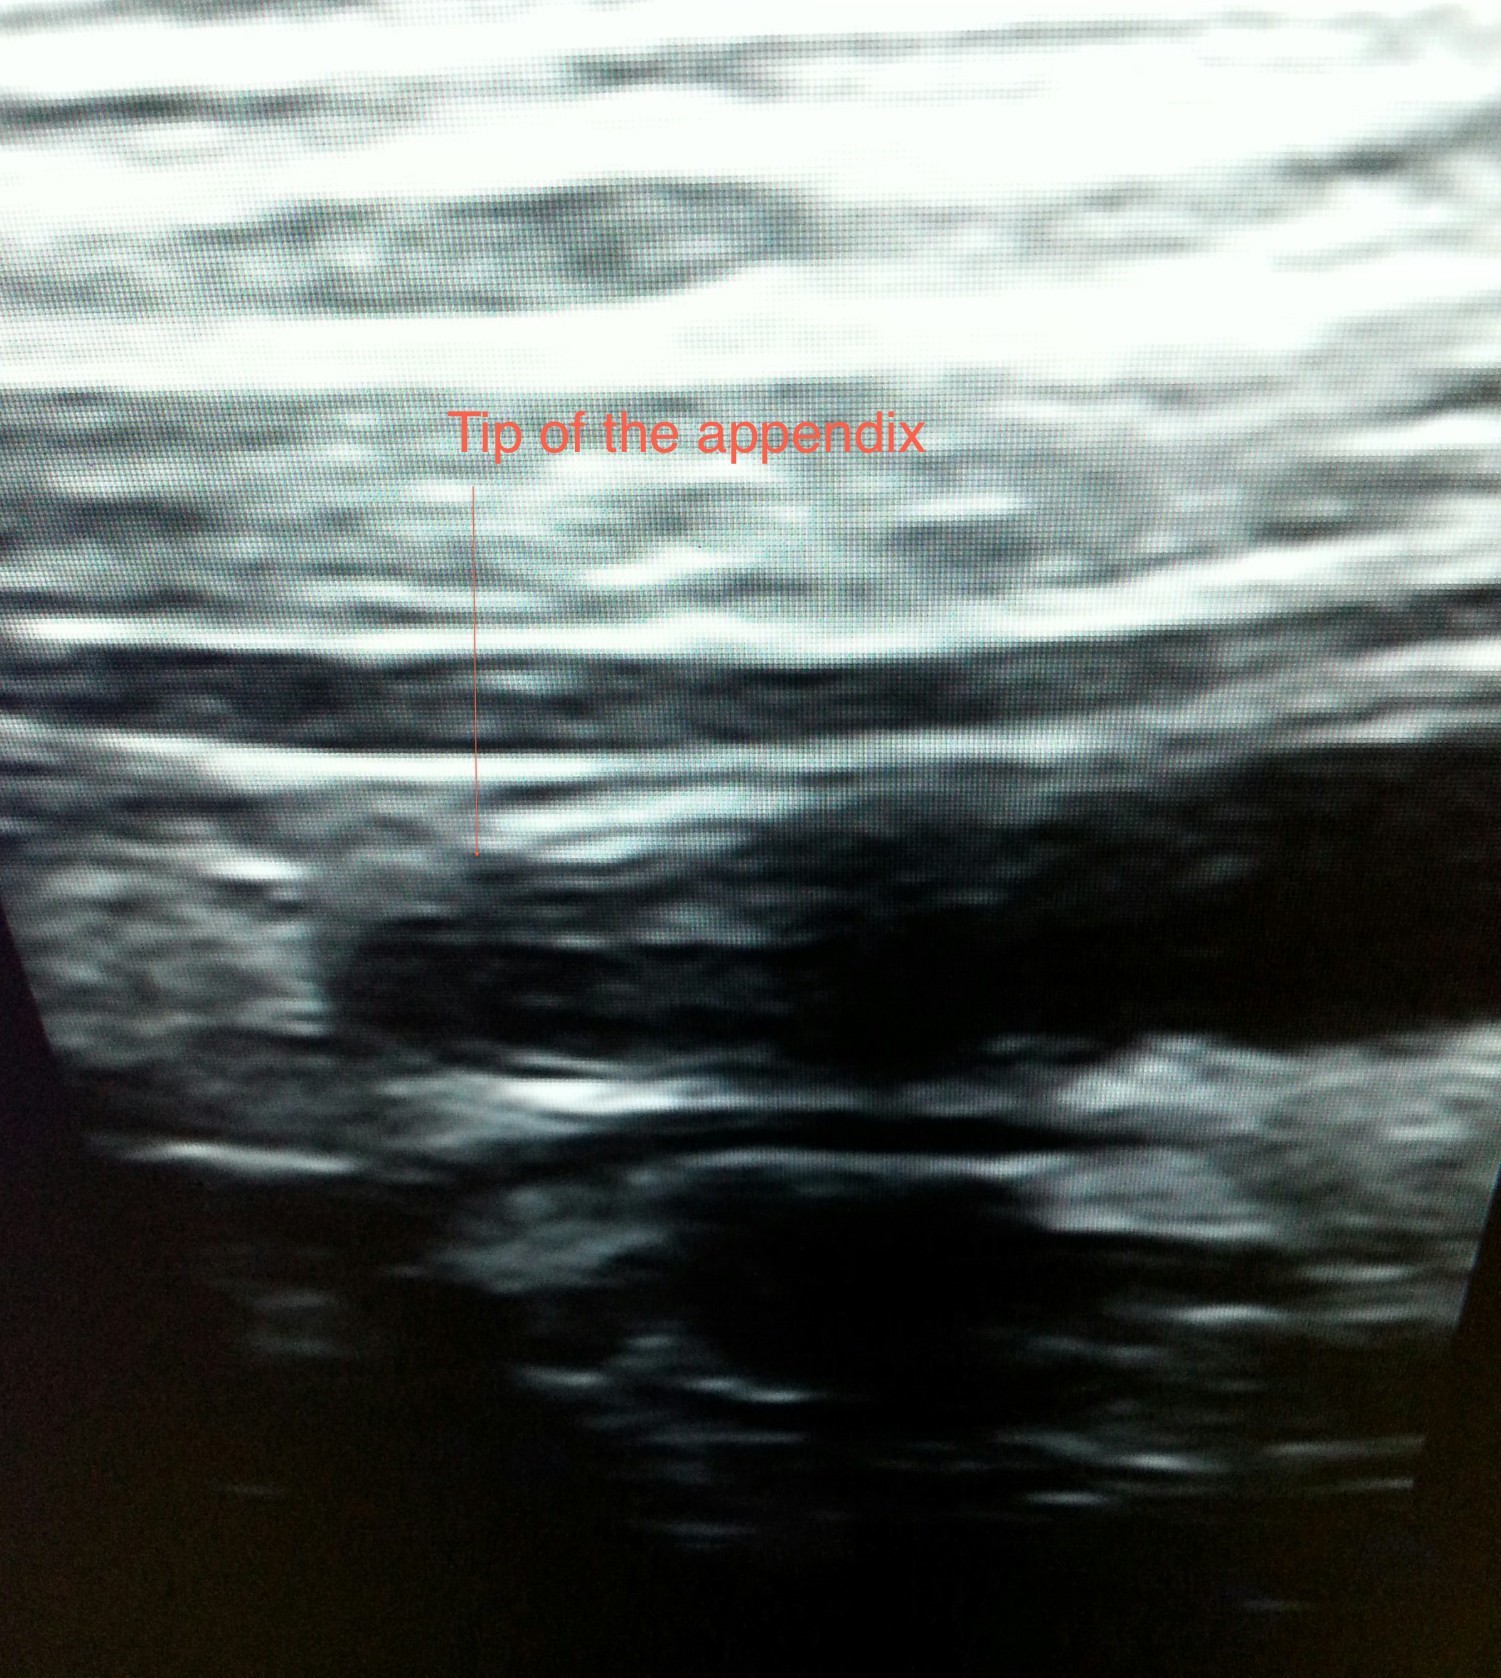

Appendicitis: Appendix is a normal organ seen in right lower abdomen. When it is thickened due to infection or obstruction it is called appendicitis. So when one has disease of appendix he/she has “appendicitis” and not “appendix”. Appendicitis is suspected(diagnosed)on the basis of findings observed and elicited by doctor along with few blood (laboratory)investigations. To confirm the clinical (by history given by the patient and doctor’s examination)diagnosis ultrasound is used. On some occasions ultrasound will not succeed in demonstrating the abnormal appendix and these are the situations which warrant a CT scan. To exclude a diagnosis of appendicitis CT is recommended.